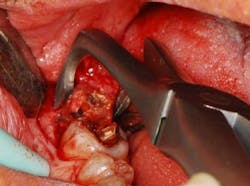

Fig. 2 — This view is taken after root planing. The lesion is a combined 1-2 wall that extends from the distal to the palate. What complicated care was that the tooth could not be extracted without incurring considerable costs. If the patient wished to replace this tooth with a fixed partial denture, she would need to have the existing seven-unit splint anterior to this tooth removed. If an implant was the desired option, the patient would need to undergo elevation of the sinus and — at the very least — wear a removable appliance until an implant could be placed and integrated, something she wished to avoid. The decision was to perform occlusal equilibration to eliminate fremitus in centric occlusion and excursive movements. Regenerative surgery was scheduled for this area that included elevation of full thickness flaps, meticulous debridement of the roots with hand and ultrasonic instruments, and root modification with tetracycline solution (Fig. 2). The root was then treated with a solution of a highly purified protein, recombinant platelet-derived growth factor (rh-PDGF-BB). The remaining/containing walls of the intrabony lesion were not ideal for space maintenance to stabilize a clot as their morphology had one to two wall components. To regenerate this site, an allograft of mineralized, freeze-dried bone (FDBA) (LifeNet Health, Virginia Beach, Va.) hydrated by rh-PDGF-BB was carefully placed into the defect to act as a biologic scaffold/clot stabilizer (Fig. 3). To further contain this graft-biologic composite, a barrier made from human chorion-amnion (BioXclude, Snoasis Medical Inc., Denver, Colo.) was placed over the graft-biologic and the flaps (Fig. 4) were secured with 6-0 expanded polytetrafluoroethylene (ePTFE) (W.L. Gore & Associates, Flagstaff, Ariz.), assuring complete closure of the site (Figs. 5 and 6).